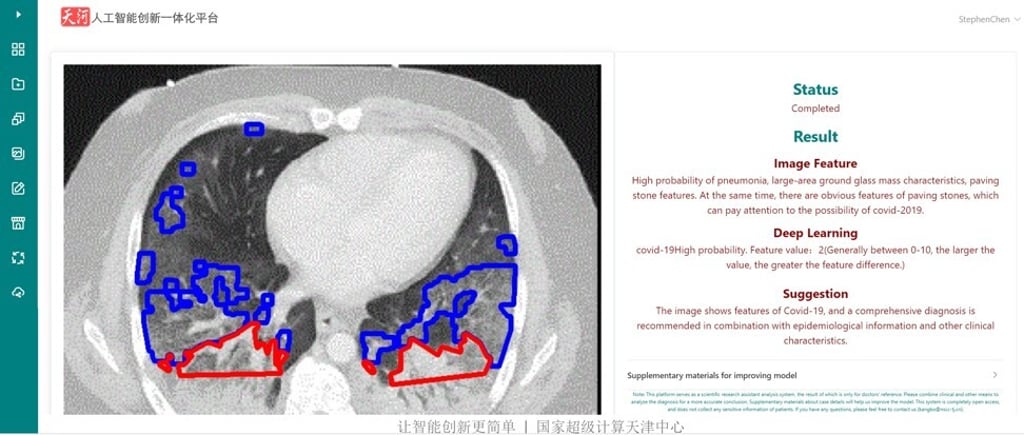

The Tianhe-1 machine detected distinguished features – suggesting high probability of Covid-19 – in the CAT image of a patient who became severely ill between July and August in North Carolina, according to a diagnosis report seen by the South China Morning Post. The machine is at the National Supercomputer Centre in Tianjin.

The features included white patches encroaching on the lower parts of both lungs, a phenomenon raising the eyebrows of some radiologists at the early stage of the outbreak because it was rarely seen in other types of pneumonia.

“The image shows features of Covid-19, and a comprehensive diagnosis is recommended in combination with epidemiological information and other clinical characteristics,” said the report generated by artificial intelligence.